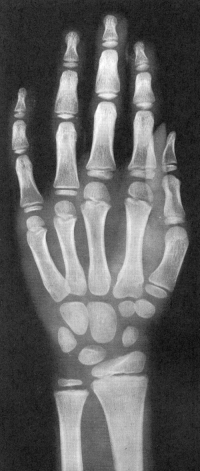

Sexo Feminino

Recém-Nascido